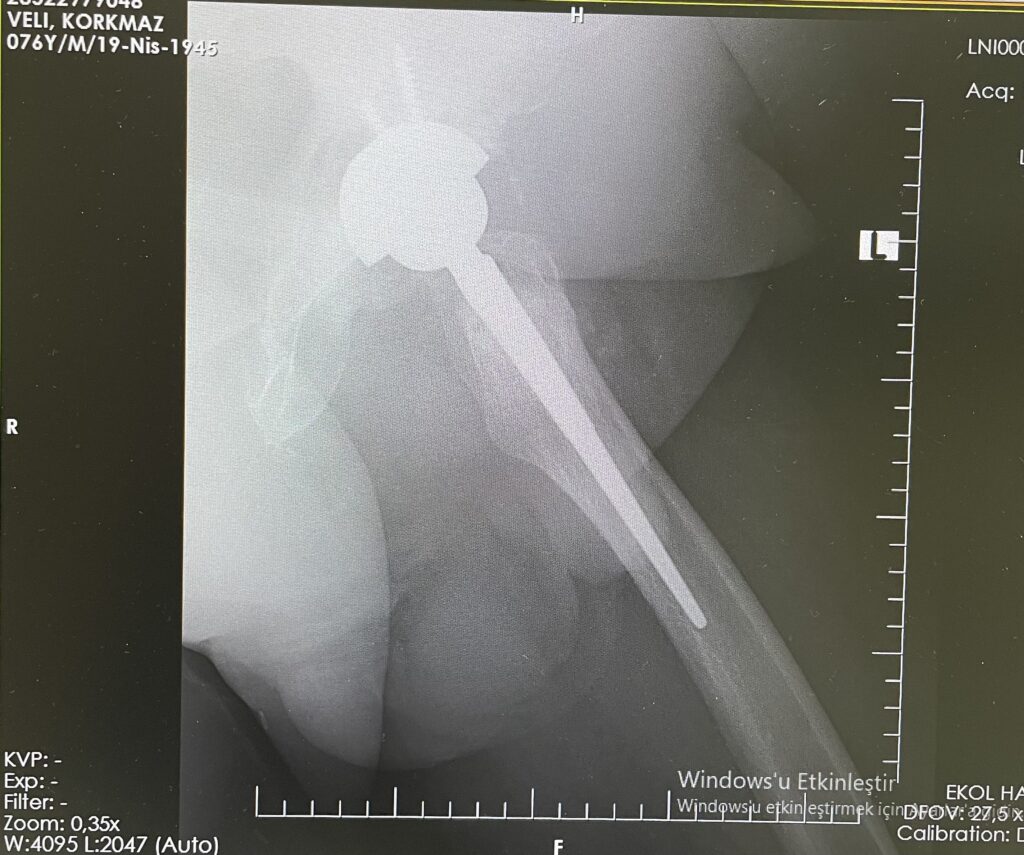

V.K.